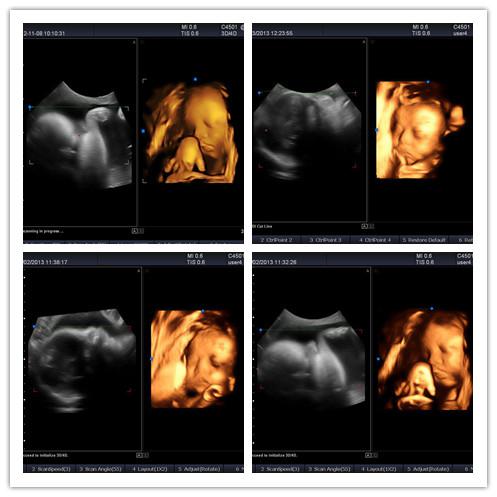

是一款全身型高檔全數(shù)字彩超,廣泛適用于腹部,產(chǎn)科,婦科,小器官,甲狀腺,血管,四肢及心臟等臨床診斷。5500秉承彩超系列全數(shù)字化彩超儀的優(yōu)良特性,采用優(yōu)越的多普勒超聲成像和圖像處理技術(shù),為用戶呈現(xiàn)更清晰細(xì)膩的圖像,同時擁有先進的3D/4D成像技術(shù),充分滿足臨床診斷需求。

4D成像